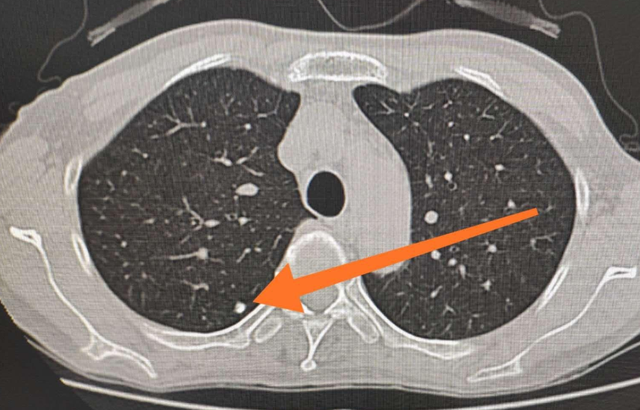

在平常日常生活,大伙儿做常规体检可能会出現肺部小结节这类状况,肺部小结节的出現很有可能是多种多样病症造成的,因此 大伙儿应当高度重视起來才行,那么肺部小结节需要医治吗?下边就为大伙儿详尽的介绍一下。

造成肺部小结节的病症是十分多的,在其中较为普遍的有肺结核和肺癌等病症,因此 大伙儿在发觉了肺部小结节以后一定要进一步查验病症的发病原因,仅有查出来发病原因才可以精确的解决肺部小结节。